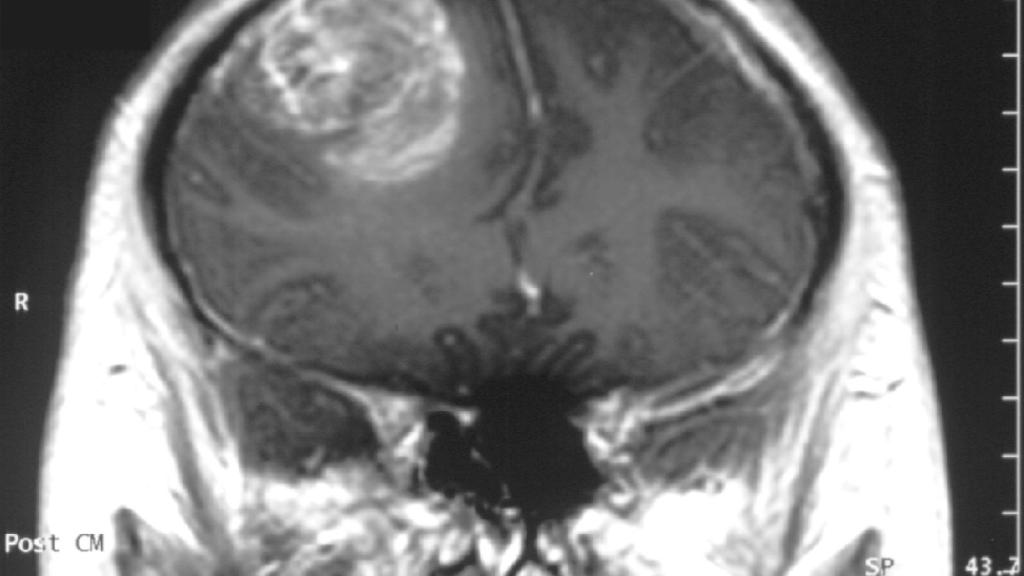

Glioblastoma_-_MR_coronal_with_contrast

El glioblastoma o GBM es uno de los tumores cerebrales más comunes en adultos, y también uno de los más agresivos: es prácticamente letal y muy dificil de operar por su gran tamaño y porque se suele desarrollar en localizaciones inaccesibles. Pero esto podría cambiar con la llegada de una técnica que desviaría el desarrollo del GBM para terminar siendo eliminado gracias a nanofibras de polímero.